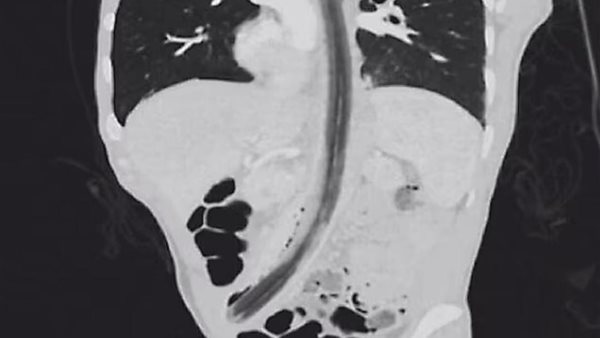

وصل رجل يبلغ من العمر 52 عامًا، إلى مستشفى في جواتيمالا بعد حوالي يوم من تناول العصا، حيث كان يشكو من آلام شديدة في المعدة، وبعد الفحص تبين للأطباء الجزء العلوي من العصا يخرج من المريء.

وأشارت التقارير إلى أن الرجل مصاب كذلك بمرض الفصام النفسي، والذي يمكن أن يسبب الهلوسة ومشاكل في السلوك، وبعد ابتلاعه العصا، كشفوا عن وجود شظايا تحفر في جوانب الأنبوب، كانت نهاية العصا تعمل أيضًا على إحداث فجوات في أسفل بطنه.

وبعد فشل محاولة سحب العصا من خلال حلقه، أزالها الأطباء جراحيًا عن طريق ثقب في معدة المريض، ثم تم تشخيص الرجل لاحقًا بأنه مصاب بالفصام، وهو اضطراب عقلي يمكن أن يؤدي إلى اضطرابات المزاج والسلوك والهلوسة.

واكتشف الأطباء بعد إزالة العصا، أنها كانت بطول قدم وعرضها حوالي 0.8 بوصة، وفحصوا كذلك الأضرار التي لحقت بالأعضاء الأخرى ولكنهم لم يكتشفوا أي تلف في القصبة الهوائية أو ثقب في الأعضاء الأخرى، مثل الكبد.